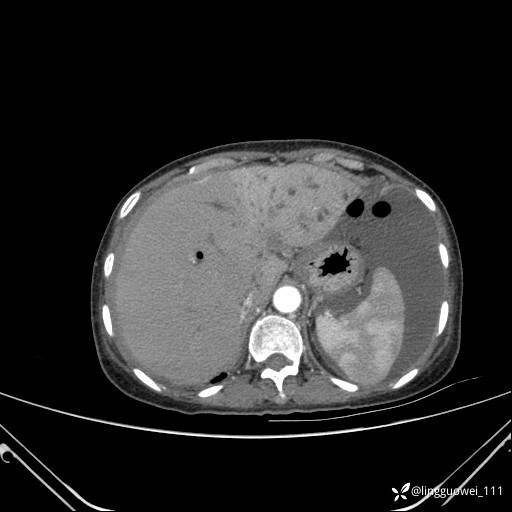

主诉:门诊行胃肠镜检查后,诉腹胀,入院检查,肝有病变吗?腹膜及腹腔的表现有特征性吗?

平扫: